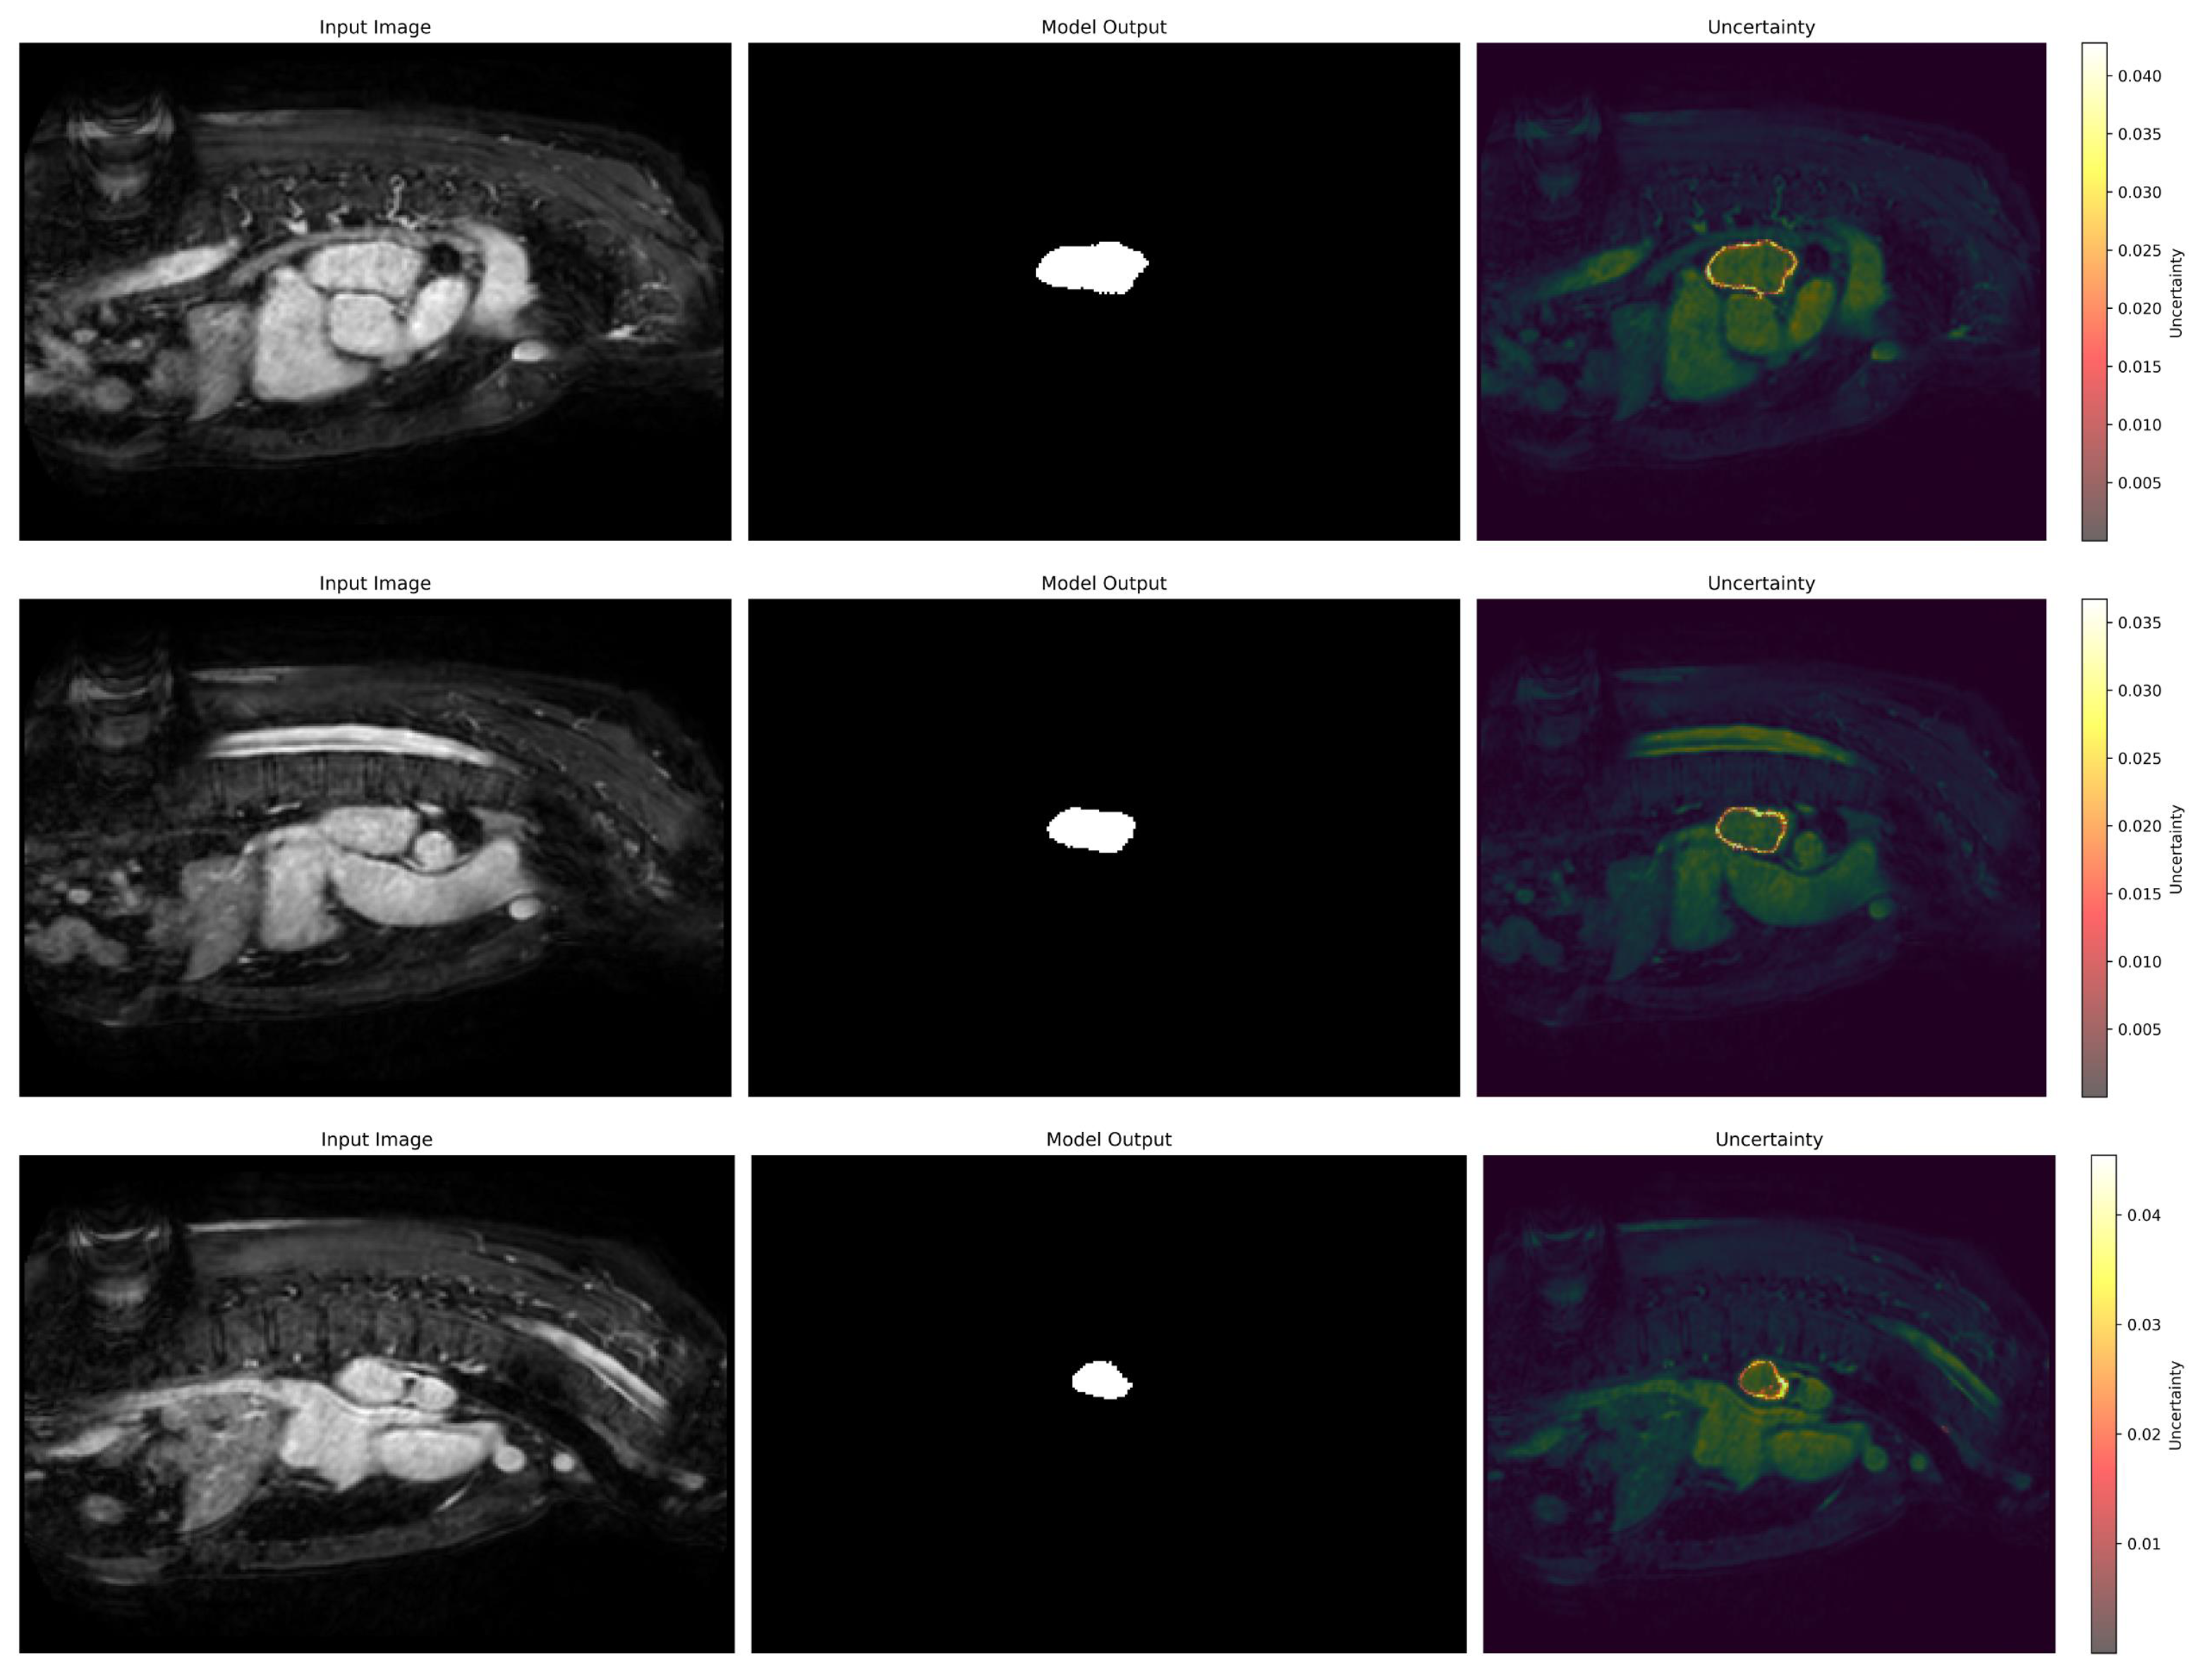

3.6. Uncertainty Estimation

We have also employed the Laplacian approximation method to estimate model uncertainty to enable a more robust prediction of our model which can help experts make decisions. Figure 11 highlights the areas where the model exhibits lower confidence along with ground truth and predicted regions. It can be seen that boundary regions exhibit lower confidence because these regions often pose challenges due to overlapping intensities or unclear anatomical delineation. Most of the segmented regions demonstrate low uncertainty, which reflects the model’s high confidence in its predictions for the majority of the structure. The integration of uncertainty estimation enhances interpretability by identifying regions that may require additional manual verification. This analysis underlines the robustness of the model and the value of uncertainty estimation in improving trust and decision-making in critical applications.

Figure 11.

Uncertainty estimation of the predicted results using Laplacian approximation.

Figure 12 illustrates the calibration error for different levels of data shift intensity across various corruptions, including rotation, Gaussian blur, Gaussian noise, hue, brightness, and contrast for the baseline model and model with Laplacian approximation. As the intensity of the data shifts increases, the calibration error for both methods generally rises, which reflects the growing challenge of maintaining reliability under more severe corruptions. The baseline model consistently exhibits higher calibration errors across all intensities, which indicates a lower ability to adapt to data shifts. In contrast, the base model with Laplacian approximation demonstrates significantly lower calibration errors. This trend is particularly noticeable at higher intensities, where the Bayesian model maintains a more stable error range compared to the wider spread of the baseline model. The results suggest that the Bayesian approach using Laplacian approximation can be explored to improve the model’s confidence calibration.

Figure 12.

Calibration error of the different data shift intensity for baseline and Bayesian models. Diamond represents the outlier.